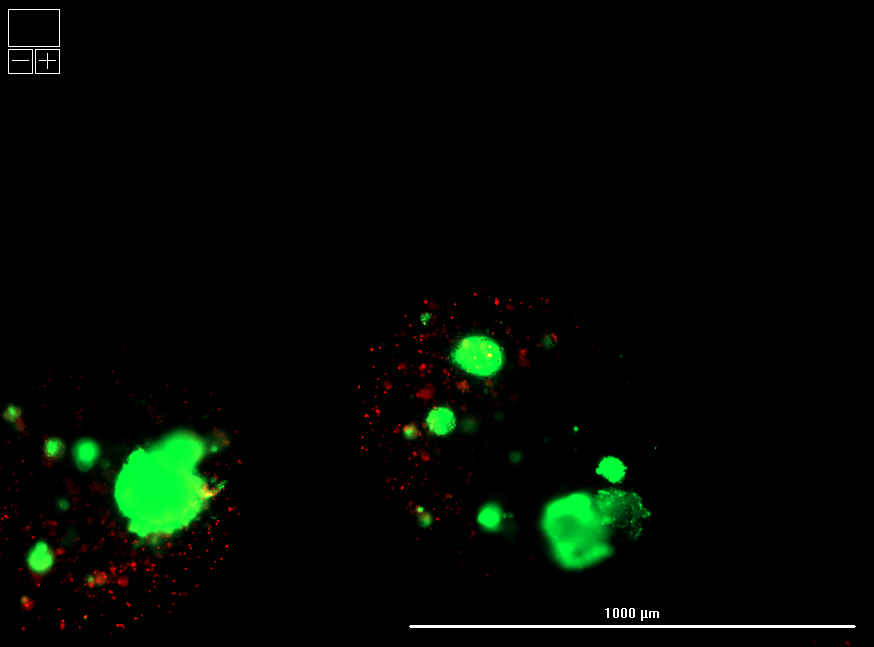

Encapsulated islets retained high viability and cellular integrity compared to standard (unencapsulated) cryopreservation, as confirmed by live/dead imaging.

Hydrogel polymer formulation #2 yielded superior survival and uniform morphology relative to formulation #1, highlighting tunability of the LiberaCell™ system.